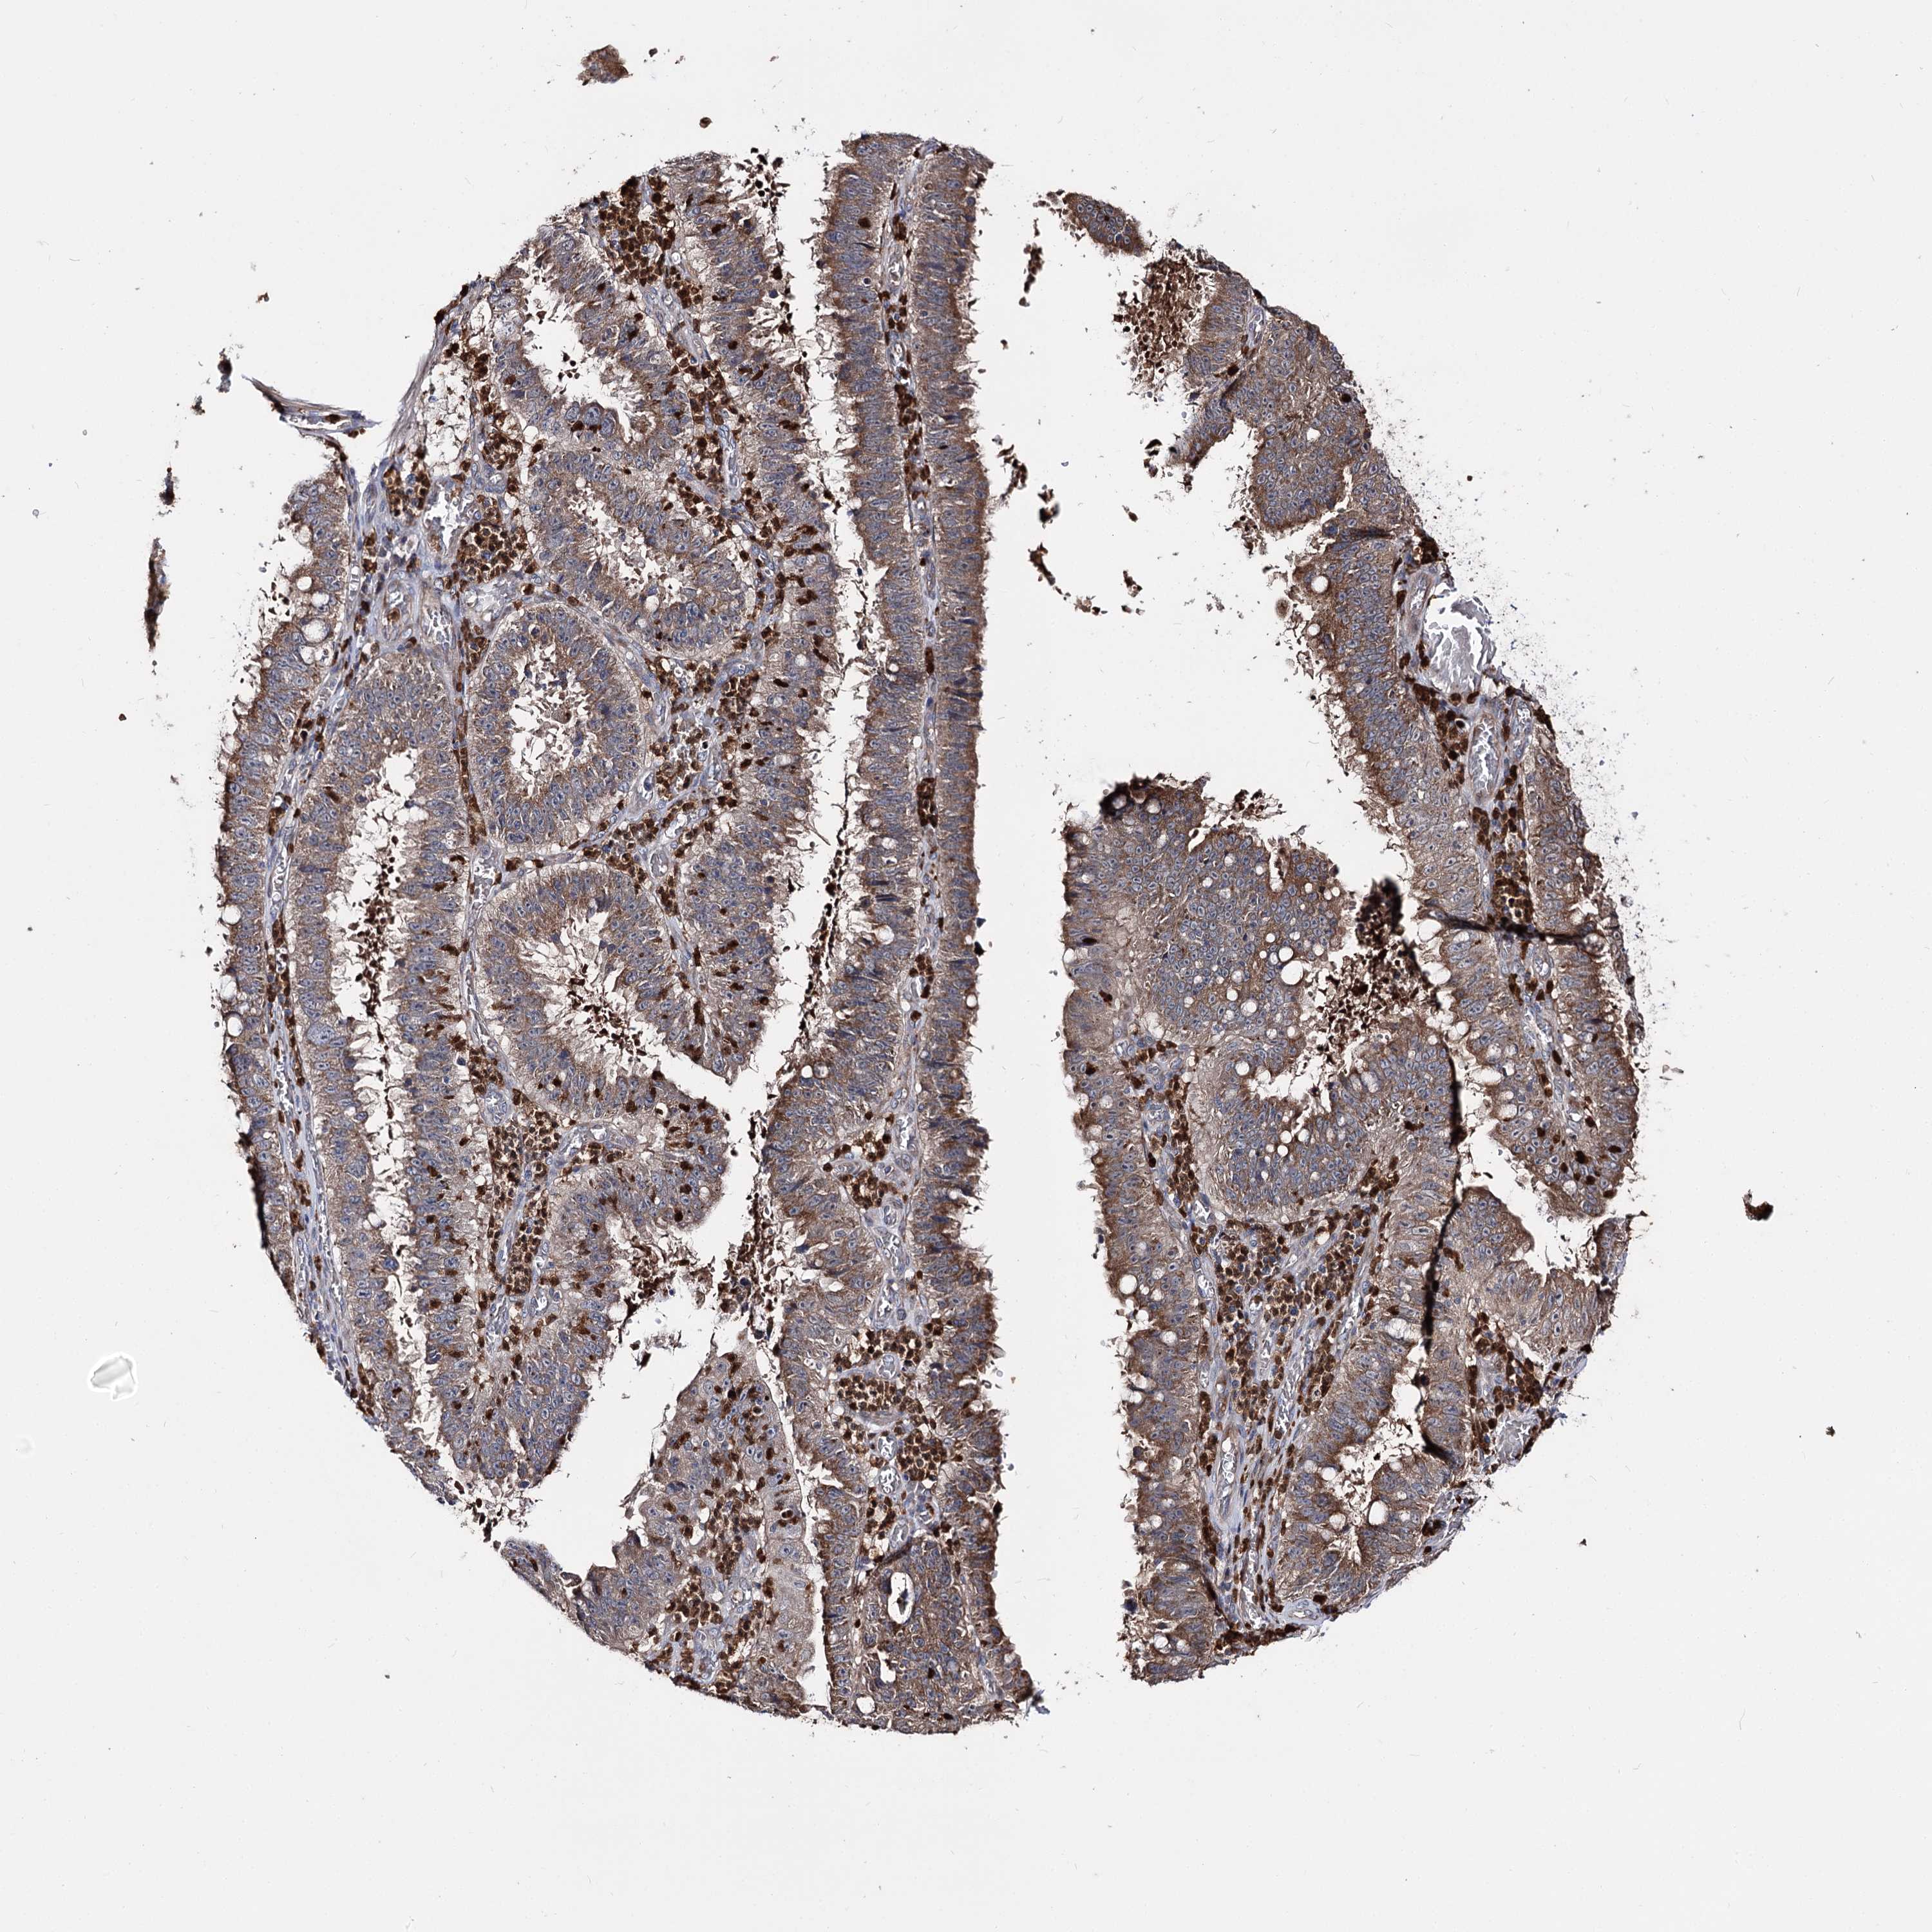

STOMACH CANCER - Protein expressioni

A mouse-over function shows sample information and annotation data. Click on an image to view it in a full screen mode. Samples can be filtered based on level of antibody staining by selecting one or several of the following categories: high, medium, low and not detected. The assay and annotation is described here.

Note that samples used for immunohistochemistry by the Human Protein Atlas do not correspond to samples in the TCGA dataset.

Antibody stainingi

Antibody staining in the annotated cell types in the current human tissue is reported as not detected, low, medium, or high, based on conventional immunohistochemistry profiling in selected tissues. This score is based on the combination of the staining intensity and fraction of stained cells.

Each image is clickable and will lead to virtual microscopy that enables deeper exploration of all samples and also displays staining intensity scores, fraction scores and subcellular localization as well as patient and tissue information for each sample.

Antibody HPA038040

Staining

High

Medium

Low

Not detected

Intensity

Strong

Moderate

Weak

Negative

Quantity

>75%

75%-25%

<25%

None

Location

Nuclear

Cytoplasmic/membranous

Cytoplasmic/membranous,nuclear

Adenocarcinoma, NOS

Adenocarcinoma, High grade